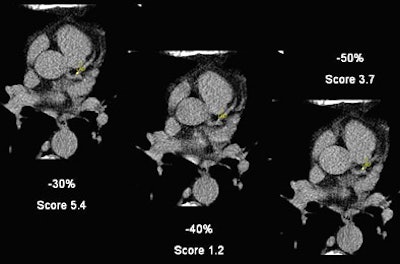

![]() |

| A small calcification within the LAD shows the variability of calcium scores based on the reconstruction interval. The -30% reconstruction interval yields a calcium score of 5.4, a -40% reconstruction drops the score to 1.208, and at -50% reconstruction it is 3.7. |